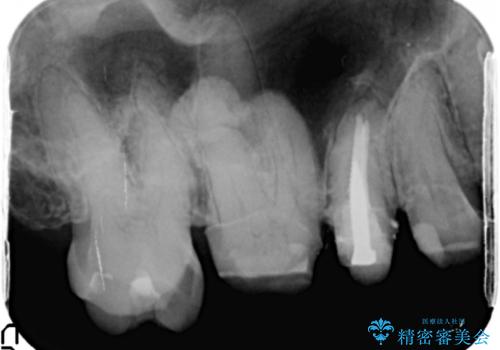

- 他院で仮歯まで入れたものの違和感があることを主訴に来院された患者様です。

違和感があると訴えたにも関わらずそのまま被せようとする他院に不安を感じ、通院をやめてしまったとのことでした。

丁寧にう蝕除去と再根管治療を行い症状の改善を確認したのち、セラミッククラウン及びセラミックインレーによる補綴を行いました。

- ¥550,000 (根管治療×1本、土台×1本、クラウン×3本、インレー×1本) ※税込費用は治療当時の料金となります